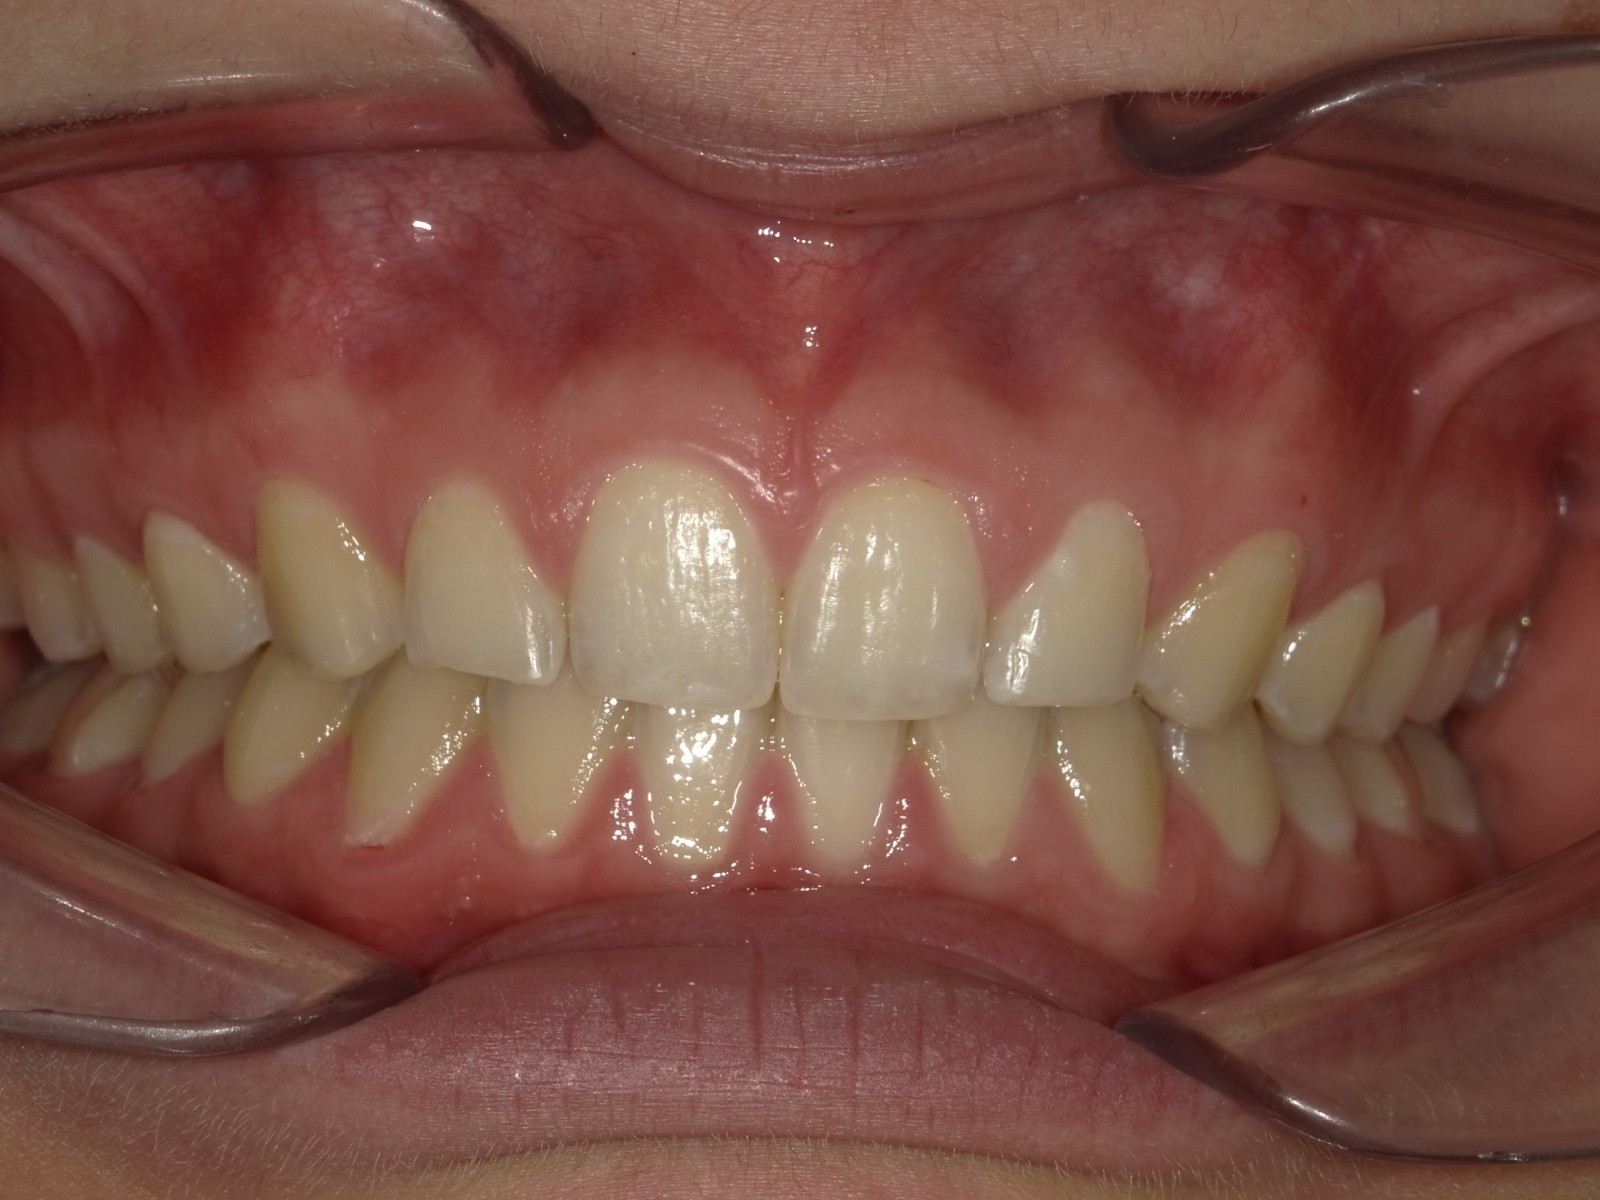

7-12 maand Distalizers